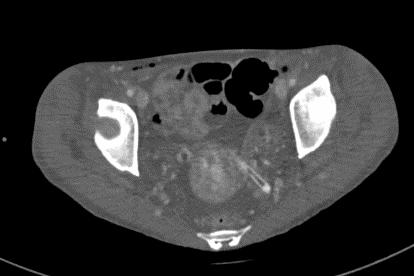

2021-4-29 CTPA:肺动脉干、左右肺动脉及其分支未见狭窄及明显充盈缺损。右肺、左肺下叶见斑片影、磨玻璃影及实变影。

2021-4-29全腹增强CT:腹盆腔散在积液,上腹腔少量积气,腹壁软组织积气,盆腔置管影。肝实质灌注不均,肝内淋巴瘀滞,提示肝功能损害。右侧见一支副肾动脉;左肾动脉提前分支。双侧附件区见多房囊状低密度影,可见环状强化,囊肿?卵泡?或其它?

患者青年女性,慢性病程;主要表现为腹胀、呼吸困难,术后出现意识障碍、II型呼吸衰竭。经呼吸机辅助呼吸、对症支持等治疗后,患者意识恢复但呼吸困难无明显改善;既往有有粉尘接触史。查体见患者极度消瘦、营养不良,双肺呼吸音粗,可闻及散在湿啰音。血气示II型呼吸衰竭、高碳酸血症,轻度贫血,低蛋白血症,电解质紊乱,炎症指标、肌酶、BNP升高,院外腹水检查示漏出液,未见肿瘤细胞;胸部CT:双肺斑片影,抗感染治疗后病灶吸收;腹部增强CT:双侧附件区分别混杂密度团块影,内见多发囊泡影;心脏彩超:右心稍大,重度肺动脉高压。